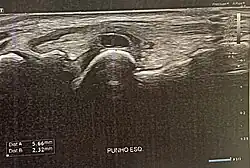

| Quisto no dorso da mão esquerda próximo do pulso | |